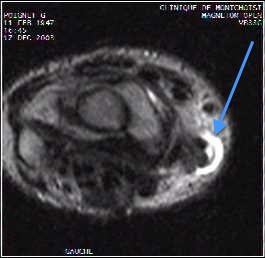

Musculosketal cases